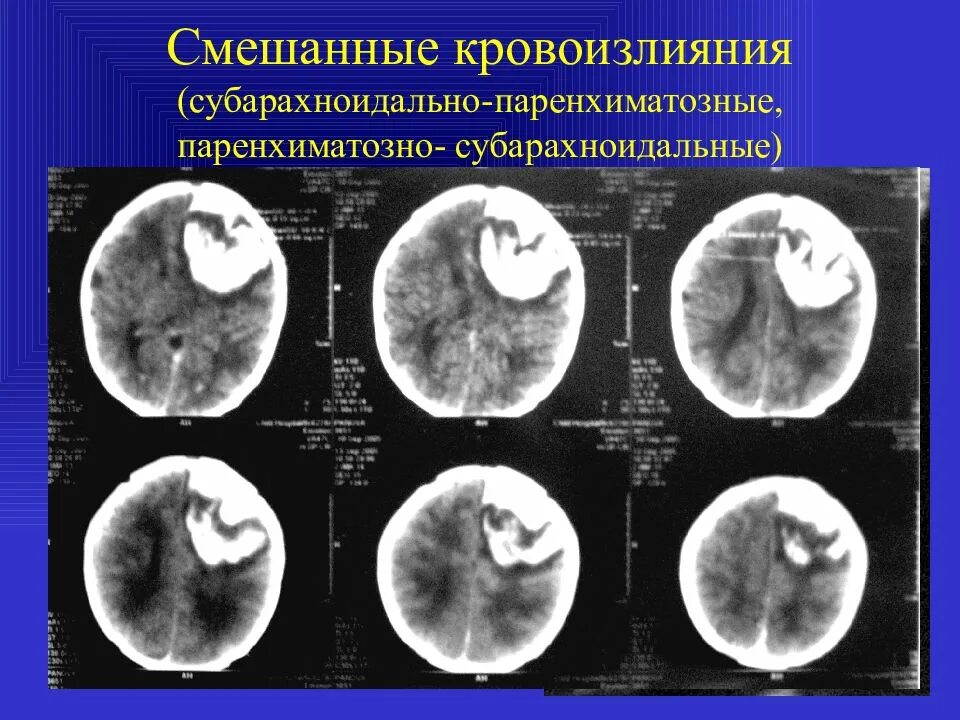

Кровоизлияние в мозг у новорожденного степени